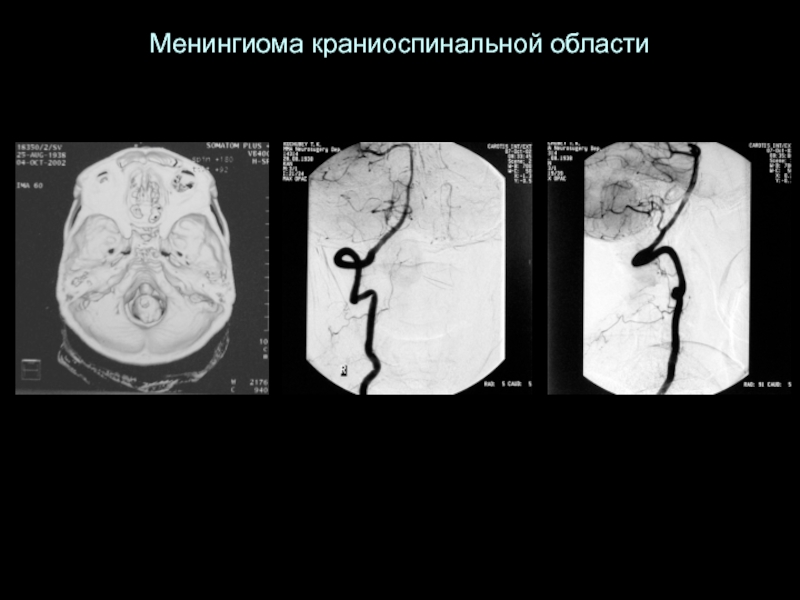

Слайд 12Менингиома краниоспинальной области

Менингиома краниоспинальной области

Слайд 13Менингиома краниоспинальной области